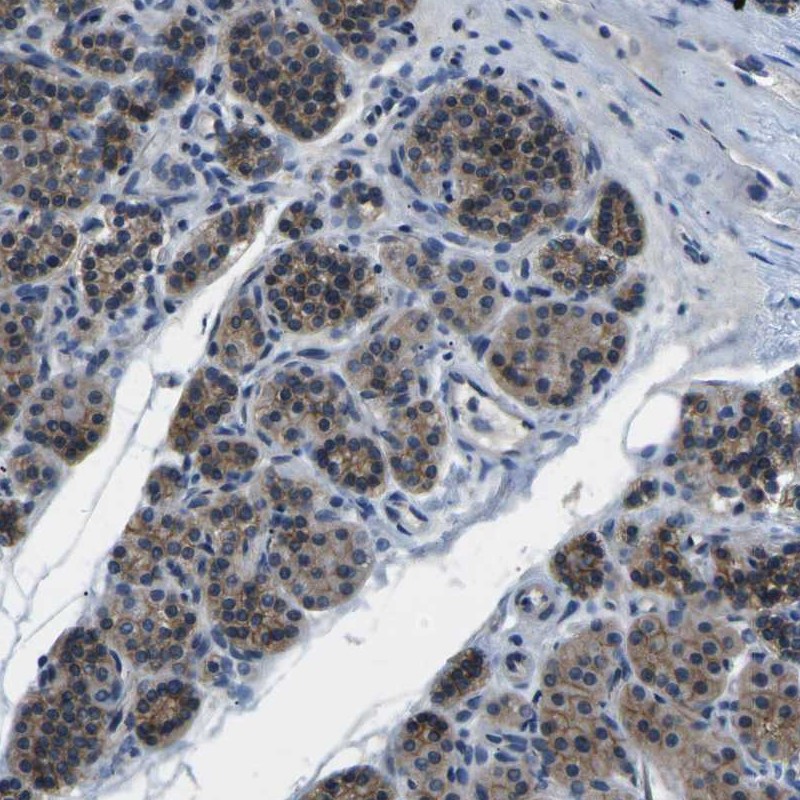

Immunohistochemistry analysis in human parathyroid gland and skeletal muscle tissues using Anti-CTNND1 antibody. Corresponding CTNND1 RNA-seq data are presented for the same tissues.